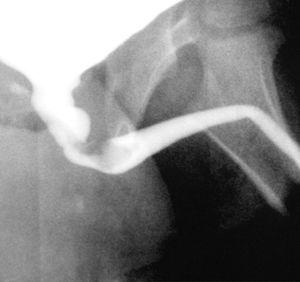

La ecografía renal y vesical muestra distensión vesical, sin hidronefrosis, litiasis, ni otros hallazgos patológicos. Ante la recurrencia del proceso se solicita cistografía miccional que demuestra la existencia a la altura de la uretra posterior de una lesión ocupante de espacio, exofítica, polipoidea que se inicia en el verum montanum, se extiende distalmente y obstruye de manera parcial la uretra (figs. 1 y 2).

Figura 1.CUMS: Fase miccional. Defecto de repleción a nivel de uretra prostática que causa disminución de la luz uretral.

Figura 2. Defecto de repleción, alargado, con base en la pared posterior de la uretra prostática (verum montanum) y que se proyecta hacia la uretra bulbar.

El diagnóstico se basa en la cistouretrografía miccional seriada (CUMS), en la cual se puede ver un defecto de repleción ovalado y móvil, de contornos lisos y bien circunscritos, que puede ocupar uretra prostática o cuello vesical1.